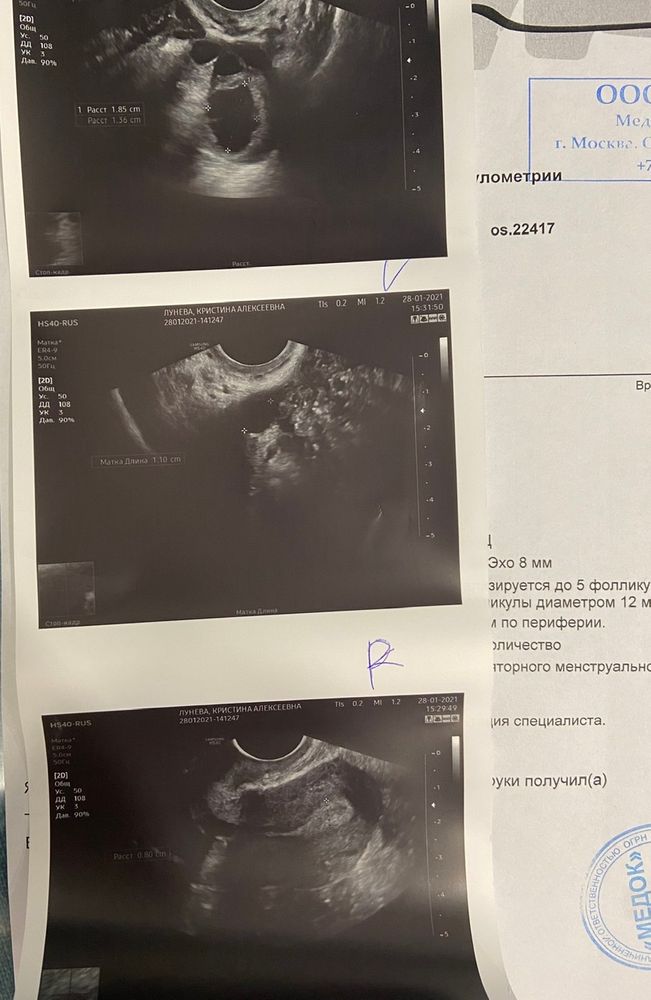

Фолликулометрия на 16дц

🔶Эндик трехслойный, М-эхо 8мм

🔶В правом яичнике до 5 фолликулов , до 11 мм.

🔶В левом яичнике фолликулы до 12 мм.

🔶Желтое тело 19Х17мм с кровотоком по периферии и оно сформировалось буквально пару дней назад, такое помятое, как изюм ещё. Есть немного жидкости после его разрыва